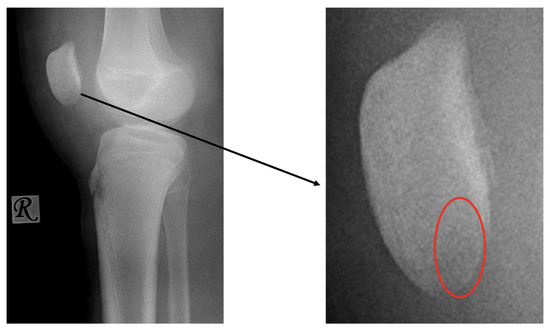

The patient was hospitalised for two days and received physiotherapy one day after surgery in the form of CPM. Weight-bearing was limited at first, with a gradual increase throughout the recovery period until week 4. Four weeks after the operation, the weight-bearing capacity was near 100% and the patient could walk without a limp, with full extension and flexion. A control X-ray was performed in the control examinations on day 10 and weeks 3, 6 and 12 (Figure 6).

Figure 6.

Postoperative X-ray presents the proper position of the osteochondral fragment of the patella (left image) on which the nails (red circle) are difficult to visualise.